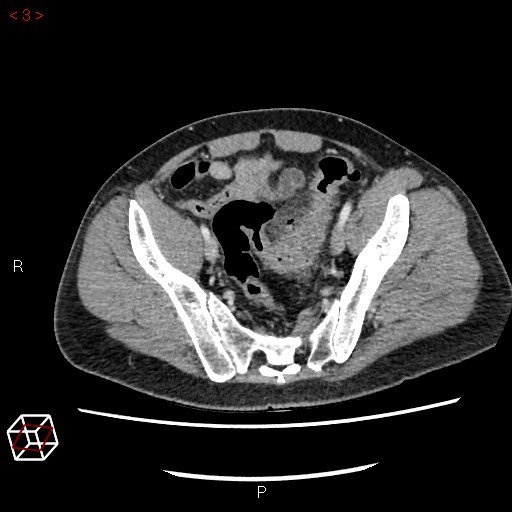

Check out this #Diverticulitis case study (with accompanying CT scan) and tell us what your preferred primary intervention would be and why! #colorectalsurgery